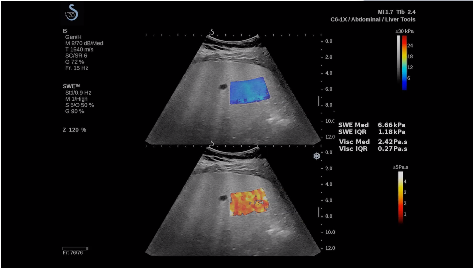

法國聲科影像(SuperSonic Imagine,SSI. Euroniex:FR0010526814)近日發(fā)表公告,宣布其研發(fā)的新一代“極速”超聲成像平臺(UltraFast Imaging),首次實現(xiàn)了肝臟的多項超聲定量評估新指標同步檢測,包括:Att PLUS,SSp PLUS和Vi PLUS等,基本涵蓋肝臟相關(guān)病理變化指征的如纖維化、脂肪變、炎癥等。據(jù)悉,此多項新技術(shù)新將搭載于新Aixplorer系列E超系統(tǒng)。

該公司首席執(zhí)行官(CEO)Michèle Lesieur女士介紹:“慢性肝病是危害公共健康的重要疾病,并呈逐年上升趨勢。目前,全世界約有8.44億人正在受到這種慢性疾病的折磨。2017年,我們已經(jīng)研發(fā)出了能夠有效輔助肝病臨床處理的部分早期診斷工具,這成為無創(chuàng)、準確評估慢性肝病嚴重程度的里程碑之一。與眾不同的是,此次的全面化技術(shù)群,由于相關(guān)定量測量技術(shù)都是基于超聲可視化圖像為基礎(chǔ),因此有可能幫助臨床醫(yī)生更高效快速地完成日常診斷治療的完整流程”。

E超相關(guān)技術(shù)已被多項多中心大樣本研究證實對于肝纖維化無創(chuàng)評估有重要意義,同時也可全面應用于乳腺、甲狀腺、肝臟、前列腺、肌骨、婦科等全身各組織器官的定量評估和鑒別診斷。在慢性肝臟方面,聲科E超的肝臟相關(guān)定量診斷技術(shù)集,于2018年獲得美國FDA認證,成為FDA歷史上首次獲批的單病種超聲全面定量解決方案。

E超是在原有B超、彩超(彩色多普勒CDFI)基礎(chǔ)上研發(fā)成功的新一代超聲剪切波彈性成像系統(tǒng),是一種能夠全面應用于表淺組織、腹部臟器,血管等方面的組織彈性成像技術(shù)。根據(jù)組織硬度彈性值的不同,有效鑒別實性腫瘤的良惡性。對于惡性病變的診斷具有較高的特異性和敏感性,尤其對于甲狀腺、乳腺、前列腺等小器官,能夠完成常規(guī)超聲不能完成的組織定量分析,可以實時、全幅、全定量獲得組織彈性(硬度)信息,為鑒別腫瘤的良惡性提供客觀、量化的診斷依據(jù)。